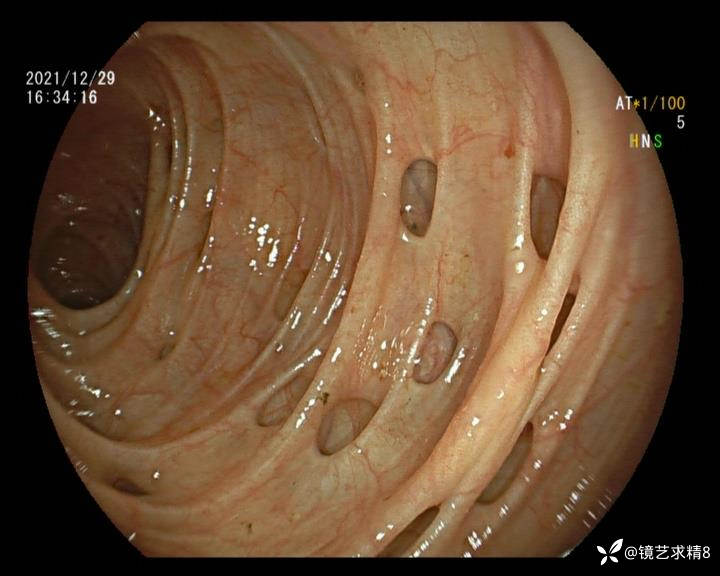

患者以消化道出血入院,胃镜未见异常,肠镜进入乙状结肠就看到很多憩室,同时还看到肠腔用清肠药后移动下来1枚尖锐的枣核,这么多憩室,这个枣核扎入憩室的机会非常大,推测应该是掉入一坑🕳就算出来还会有很多坑🕳🕳🕳等着,掉入憩室内很容易刺破血管,这可能就是消化道出血的原因,继续前进可以看到有一些憩室内翻,还有一些息肉,问题来了,那么多憩室,犯罪分子是抓住了,它在那些憩室内作过案?到达回盲部后挨个冲洗,但憩室大小又不足以把镜头进入憩室内观察,针对有血块的憩室冲洗后可疑出血的以夹子闭合或套扎,取出枣核,如果有锥形透明帽可能钻入憩室精准电凝效果更好,若内镜下操作失败介入治疗成功率更高,经内镜下治疗后观察未再出血出院。

亚洲人群结肠憩室主要发生在右半结肠,然后随着年龄的增长而延伸到左半结肠和双侧结肠。相比之下,欧美人群80%的结肠憩室好发于左半结肠,其中乙状结肠憩室占 70%,而大多是假性憩室。 然而,与憩室炎主要发生在左半结肠不同,东西方人群的憩室出血均主要发生在右半结肠,可能与右半结肠的憩室更宽大及憩室血管更易受到损伤相关。